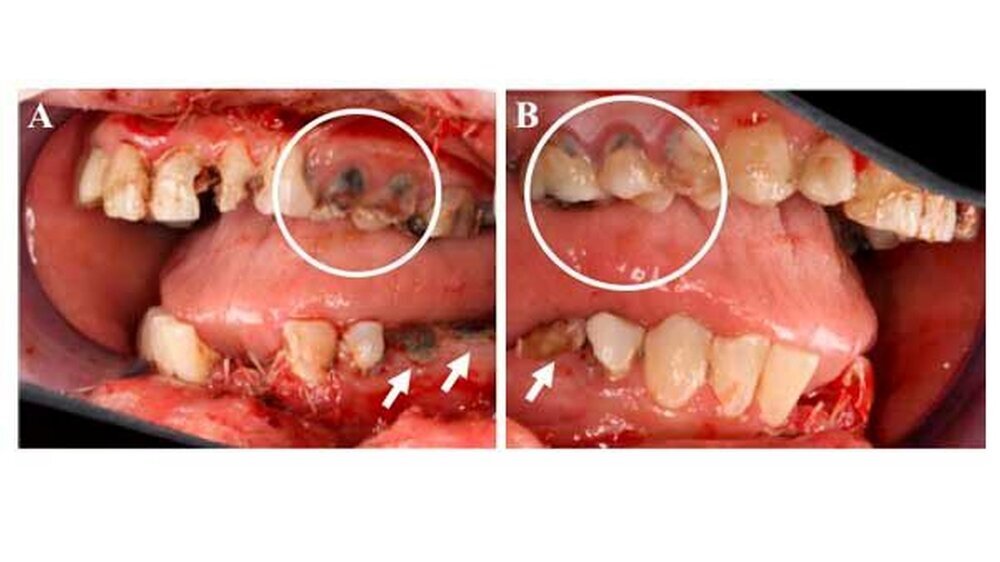

Die weitere klinische Inspektion ergab intraoral den Befund eines kariös tief zerstörten Restzahngebisses mit multiplen, teils gelockerten, nicht erhaltungswürdigen Zähnen.

Einige Tage später stellte sich die Patientin erneut in unserer Ambulanz mit einer ausgeprägten Wundheilungsstörung, einer beginnenden Superinfektion sowie einer beginnenden Weichgewebenekrose vor.

) erfolgte in Vollnarkose eine Wundrevision und Reposition der Nasenbeinfraktur. Zusätzlich erfolgte - mit Ausnahme der dentes caninii - die operative Entfernung der tief zerstörten und nicht erhaltungswürdigen Restbezahnung des Ober- und Unterkiefers in Kombination mit einer modellierenden Osteotomie sowie einem plastischen, speicheldichten Wundverschluss.